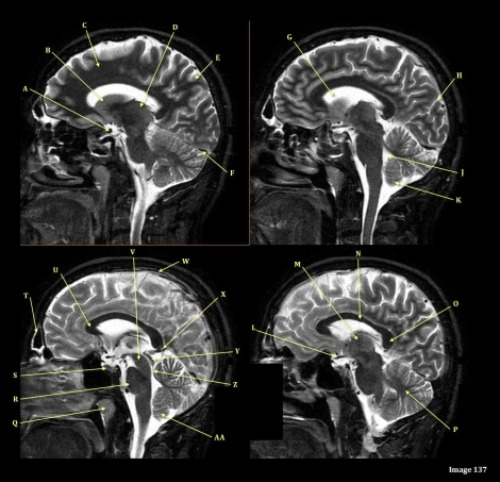

Letter C in Image 136 is pointing to:

A. Anterior frontal veins

B. Posterior frontal veins

C. Parietal veins

D. Internal cerebral veins

E. Vein of trolard

Letter Q in Image 136 is pointing to:

A. Right transverse sinus

B. Left transverse sinus

C. Right parietal veins

D. Left parietal veins

E. Right sigmoid sinus

F. Left sigmoid sinus

Letter F in Image 136 is pointing to:

A. Anterior frontal vein

B. Posterior frontal vein

C. Parietal vein

D. Internal jugular vein

E. Internal cerebral vein

Letter D in Image 136 is pointing to:

C. Sigmoid sinus

D. Superior sagittal sinus

Letter J in Image 136 is pointing to:

Letter M in Image 136 is pointing to:

Letter R in Image 136 is pointing to:

A. Rosenthal vein

C. Basal vein

D. Internal cerebral vein

F. A and / or C

Letter P in Image 136 is pointing to:

Letter G in Image 136 is pointing to:

A. Superior sagittal sinus

B. Right sigmoid sinus

C. Left sigmoid sinus

D. Right transverse sinus

E. Left transverse sinus

Letter K in Image 136 is pointing to:

Letter E in Image 136 is pointing to:

B. Vein of trolard

C. Torcular herophili

E. Posterior sigmoid sinus

Letter B in Image 136 is pointing to: